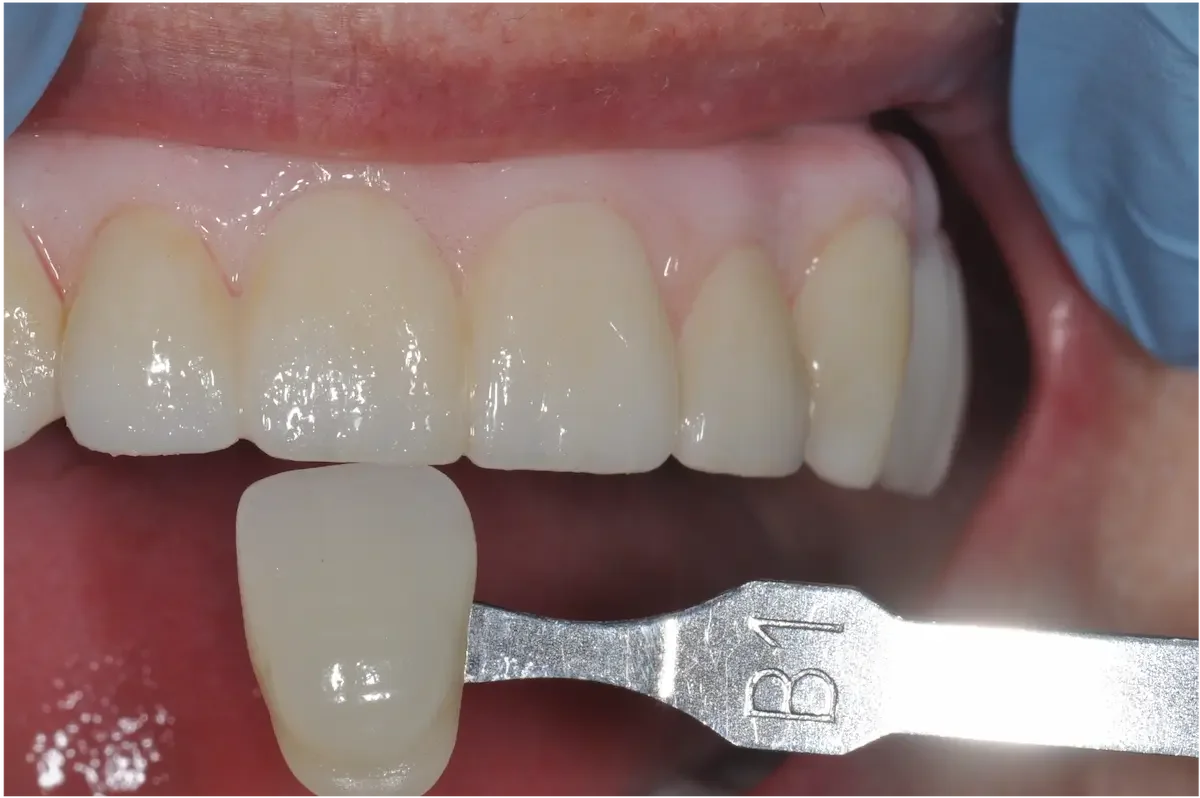

Unlike molars, where strength matters to a higher degree, replacing a front tooth is has much to do with aesthetics, symmetry, and subtlety, in addition to bite force management.

Any tiny mismatch is obvious. The color, shape, gumline — everything has to match the neighboring teeth.

We’re working in the “esthetic zone.” This area demands precise planning, sculpting, and soft tissue support. Thankfully all our doctors have advanced training in cosmetic dentistry.

Once everything is stable, we place the final custom crown. Shade, translucency, shape, and surface texture are all matched to your natural teeth so the implant blends in seamlessly.